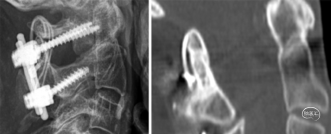

图1. 1例患者术后1年随访时侧位X线片(左)和CT矢状位成像(右)。CT清晰显示融合块;齿突骨折处有前方和后方的骨皮质愈合。